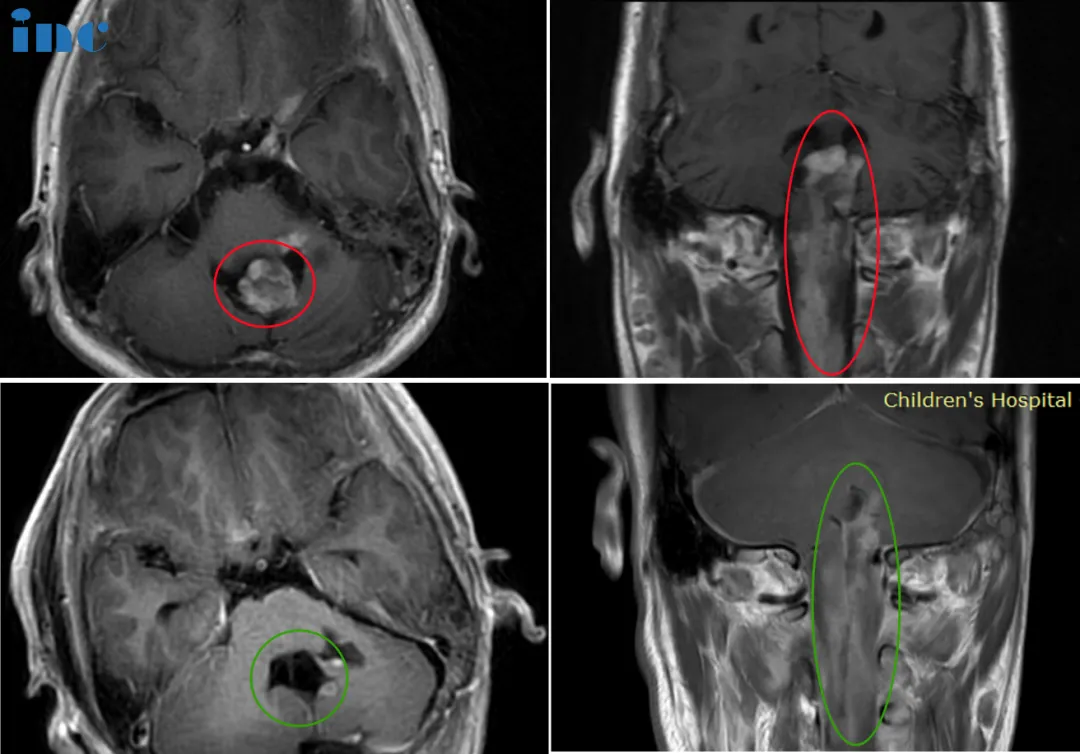

33岁的郑女士2016年因晨起颈部疼痛和自感右上肢无力,提示颈椎椎管占位性病变,期间郑女士因为怀孕未行任何治疗。然而2021年前患者感到症状加重,肢体出现无力及麻木以及温度异常。2022年8月行核磁复查,病变较2017年范围明显增大,累及延髓和颅颈交界区,且向下方延伸到整个颈部脊髓以及一直到一胸椎水平,病变累及范围近15cm。为了更好的陪伴着孩子的成长,郑女士决定寻求国际教授的治疗……

▼巴教授术前术后影像对比图片

巴教授评估回复:

“当然,病人需要手术治疗,而且应该在肿瘤比现在小的时候更早接受手术。但是,正如我从视频中看到的,由于病人的神经功能状态相当好,手术还是可行的,也是必要的。切除率在我手当中将至少95%,也许我甚至可以做到比这个更多”

2022年11月巴教授疑难示范手术期间,2022年11月23日,这台长达12个小时的高难度手术在苏州独墅湖医院顺利完成,手术时长相当于两台手术——延髓和脊随髓内。参与全场手术的国内医生无不惊叹教授无与伦比的手术技术,感叹哪怕在国际范围内,这样大的一个手术也是少见。

33岁男性-脊髓髓内室管膜瘤

40岁刘先生因为出现持续的脖子肩膀酸痛、手抖、平衡性差、头晕等症状就医检查,诊断为脊髓髓内肿瘤,多地咨询后都因为手术易致残建议不手术,但是不手术,症状只会越演越烈。

巴教授邮件回复:

“目前我会给病人提供手术探查,目的是获得精确诊断的材料。如果病变可以做手术,当然会切除。如果不能,由于各种形态学的原因,这是可能的发生的,那么能做的操作就只能是活检。”

2021年教授疑难示范手术期间,INC巴教授成功为刘先生手术,脊髓髓内肿瘤得到全切,术后病理为脊髓髓内室管膜瘤,室管膜瘤为良性肿瘤,全切手术后预后好,回首患病到成功手术的治疗之路,他庆幸自己及时做出了正确的选择,争取到了巴教授的手术机会,给自己争取到了较好的预后结果。

14岁的睿睿2016年底偶发左手抓握力弱,2017年初查出神经节细胞瘤;医生表示肿瘤生长缓慢,无法全切,还会复发,故保守观察。2021年底,双侧肢体无力加重,左侧更明显。2022年睿睿再次就医检查,肿瘤位于脑干延申至脊髓,肿瘤占位大小33*42*94mm。在国内某医院做了一开始开颅手术,虽仍有不少残留,但手术取得完整病理,肿瘤导致的病情有适当好转,为后续手术提供了清晰的思路、争取了时间……

巴教授远程邮件回复

“是的,男孩可以接受手术,而且,为了生存,这是他中期能采取的机会。如果不做手术的话,由于肿瘤的进展,尽管已经做过气管造口术,男孩早晚会出现很严重的吸入性肺炎和逐渐恶化的四肢麻痹。因此,应该给他生存的机会,幸运的话临床症状在程度上会有好转,肿瘤不是恶性的”